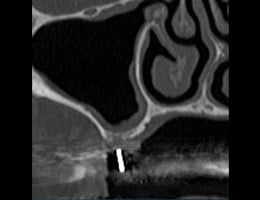

2. サイナリフトという技術を用いて、骨を増やしインプラント治療ができるようにします。

3. 顎の骨が増えた所に10mmのインプラントを埋めることが出来て、しっかり噛めるようになりました。